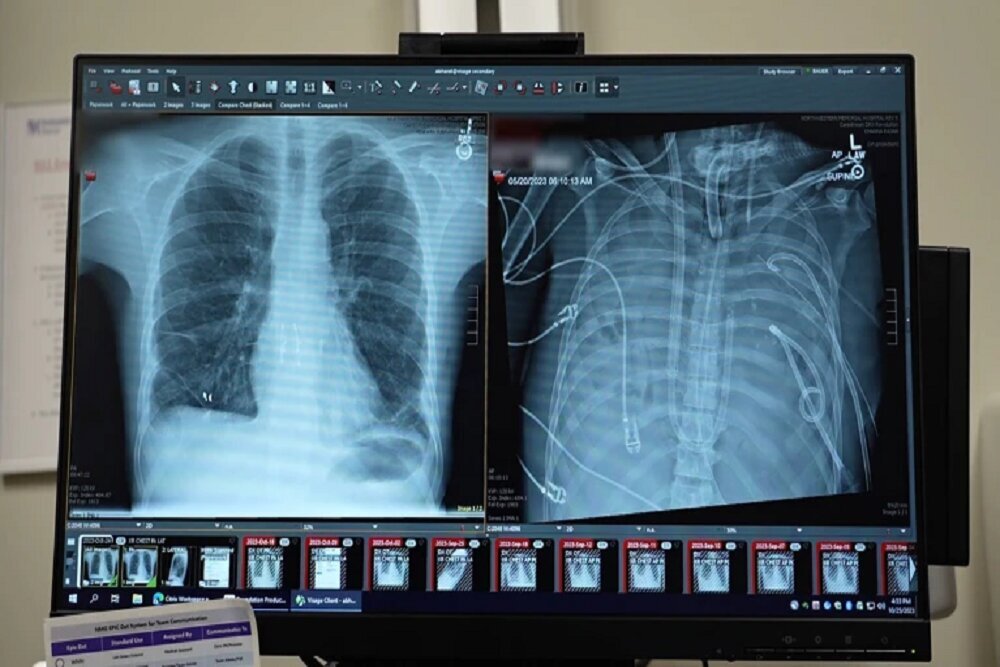

قبل از قرار گرفتن روی سیستم ریه مصنوعی، این مرد دچار سندرم حاد دیسترس تنفسی شده بود که یک وضعیت اغلب تهدیدکننده حیات است که در آن ریهها نمیتوانند اکسیژن کافی جذب کنند و این مشکل توسط ویروس آنفلوانزا ایجاد شده بود. سپس او روی ونتیلاتور قرار گرفت، اما دچار عفونت مقاوم به دارو شد. این عفونت باعث شد قسمتهایی از ریههای او پر از چرک شود و او وارد شوک سپتیک شود که در این مرحله قلب و کلیههایش شروع به از کار افتادن کردند.

بهارات میگوید: او خیلی بیمار بود، دچار ایست قلبی شد و در حال مرگ بود. از آنجا که این مرد خیلی بیمار بود که پیوند ریه دریافت کند، گروه پزشکان تصمیم گرفتند ریههای او را که منبع عفونت بود، بردارند.

به طور شگفتانگیز، مرد شروع به بهبود سریع کرد. در عرض ۴۸ ساعت، او همه داروها برای حمایت از فشار خون را کنار گذاشت، عملکرد کلیه او کاملا بازیابی شد و قلب او به طور طبیعی کار میکرد. در این مرحله، مرد پیوند دو ریه را دریافت کرد و سالها بعد هیچ نشانهای از رد عضو یا اختلال عملکرد ریه نشان نداد. اکنون تقریبا سه سال از انجام این کار گذشته است و حال بیمار واقعا خوب است.

اگرچه فناوری به نام اکستراکورپورال ممبران اکسیژناسیون (ECMO)، وجود دارد که میتواند کار ریهها را انجام دهد و برای اکسیژنرسانی به خون و حذف دیاکسید کربن کاربرد دارد، ریههای فرد در بدن او نگه داشته میشوند که قلب را پایدار نگه میدارد. راجرز میگوید سیستم جدید به قلب متصل است و نسخه اصلاحشدهای است که فشار مناسب برای جریان خون به و از قلب را حفظ میکند.